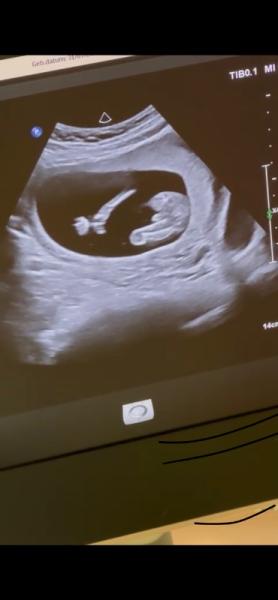

Hallo, wollte mal fragen was ihr dazu sagen würdet, für ein Mädchen ist es ja wohl deutlich zu groß oder? Die Ärztin meinte sie ist sich relativ sicher das es ein Junge ist man kann es aber nie genau sagen, Villt sag es ja bei jemandem ähnlich aus

Bild zu Geschlecht 16.ssw - Schwanger - wer noch? Rund um die Schwangerschaft

Huhu würde auch sagen ein Junge! Sah bei meinem Sohn auch so aus . Alles gute